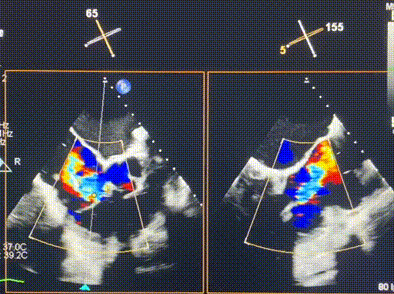

術(shù)前超聲提示重度三尖瓣反流

術(shù)后超聲顯示僅殘余微量瓣周漏